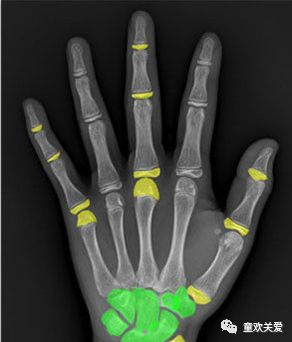

2)骨龄评测方法-图谱法

- 与标准骨龄X线图谱比较,观察手腕部各个骨和骨骼发育阶段X线特征,即成熟度标志。

- 各腕骨骨化中心正常呈现程序,即头状骨,钩骨,三角骨,月骨,舟骨,大多角骨,小多角骨,豌豆骨。

- 在一张手腕X片上,可能有少数骨骼发育超前或者落后,则应以片上大多数骨骼发育水平来判断。

- 青春期和以后,着重对比骨骺端融合过程,然后参照各骨发育情况

- 骨发育水平介于两张标准图谱之间,可用最接近一张为准